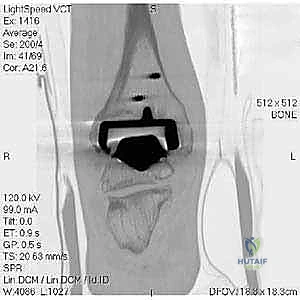

مراجعة مفصل الكاحل الصناعي هي إجراء جراحي ضروري لمعالجة المشاكل التي قد تنشأ بعد الجراحة الأولية، مثل كسور الكعبين أو عدم استقرار المفصل. يتضمن العلاج التشخيص الدقيق عبر الأشعة السينية والتصوير المقطعي، يليه التدخل الجراحي لتثبيت الكسور واستعادة وظيفة الكاحل، مع التركيز على التعافي المبكر.

تُعد جراحة مراجعة مفصل الكاحل الصناعي (Revision Total Ankle Replacement) من الإجراءات الجراحية المتقدمة والبالغة الدقة في عالم جراحة العظام الحديثة. لا تقتصر هذه الجراحة على مجرد استبدال مفصل تالف بآخر جديد، بل هي عملية إنقاذ معقدة للغاية تهدف إلى معالجة المشاكل الميكانيكية والبيولوجية التي تنشأ بعد الجراحة الأولية. من أبرز هذه المشاكل: الفشل الميكانيكي للمفصل، تحلل العظام (Osteolysis)، أو حدوث كسور معقدة في الكعبين (Malleolar Fractures) المحيطة بالمفصل الصناعي. يتطلب هذا الإجراء تقييماً سريرياً وشعاعياً دقيقاً يشمل التصوير المقطعي ثلاثي الأبعاد والأشعة السينية، يليه تدخل جراحي دقيق لاستعادة التوازن الحيوي والميكانيكي للكاحل والحفاظ على الطرف من البتر أو الدمج.

- التصوير المقطعي المحوسب (CT Scan): وهو الأداة الذهبية لتقييم "المخزون العظمي" (Bone Stock). يوضح بدقة حجم الأكياس العظمية ومقدار العظم المفقود الذي سيحتاج لترقيع.